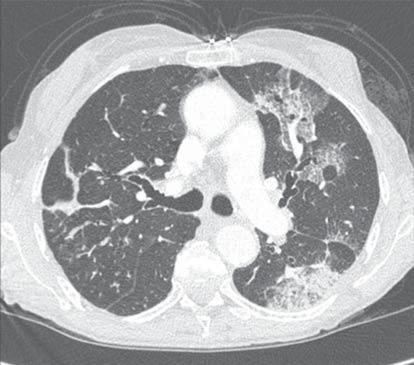

Une radiographie et un scanner du thorax sont

D aspect typique d'œdème pulmonaire aigu E

À ce stade, parmi les arguments cliniques et radio-

(maladie de Wegener) ?